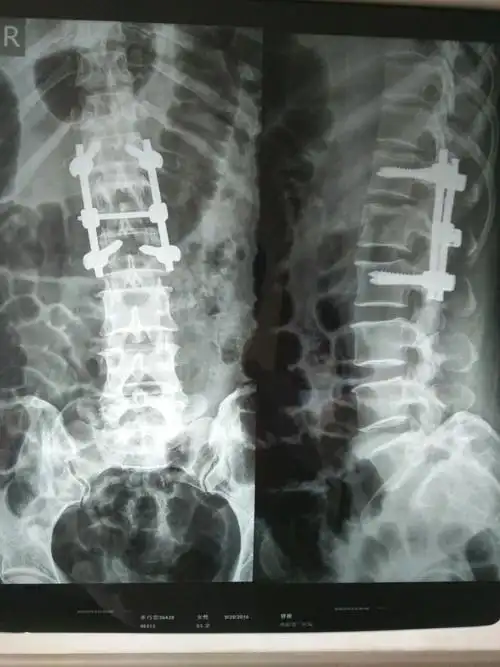

脊柱爆裂性骨折椎弓根螺钉固定南京邦德骨科医院赵加军